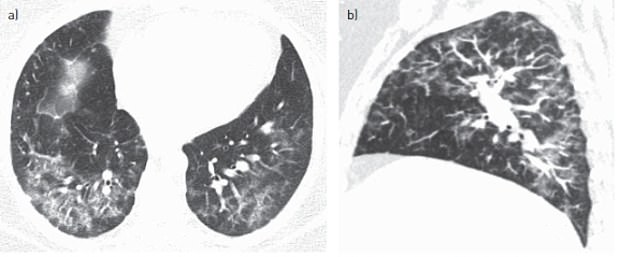

The CT scan revealed that the incurable lung disease had damaged her lung tissue to capture other cells and create giant cells in the lungs. This rare lung disease creates breathing difficulties due to the build-up of cells that block the lung functions.